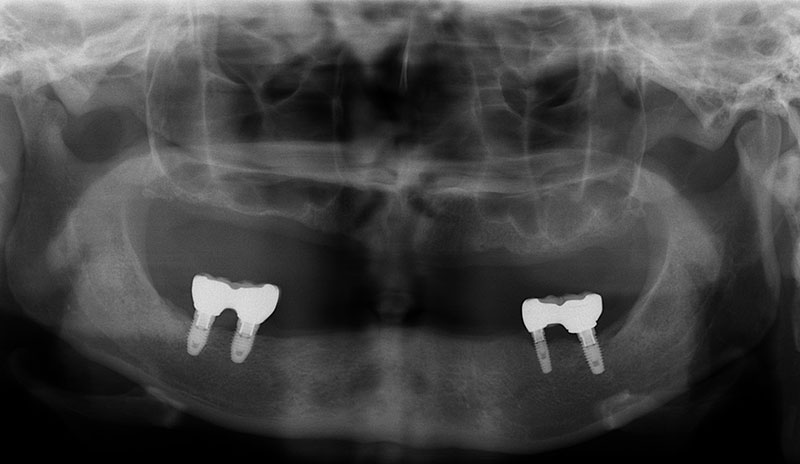

植牙的目的,就是將原來已經失去的咬合能力復原,因此必須更謹慎的評估患者骨質的密度、高度和寬度是否都能滿足植牙的條件。

許多人缺牙多年後才想要植牙,但此時齒槽骨已萎縮,少了堅固的骨頭做為牙根的支撐當然不會穩固。因此可以把補骨想成幫牙根打地基,有了堅硬的地基再植入人工牙根,植牙效果才會穩定耐用。